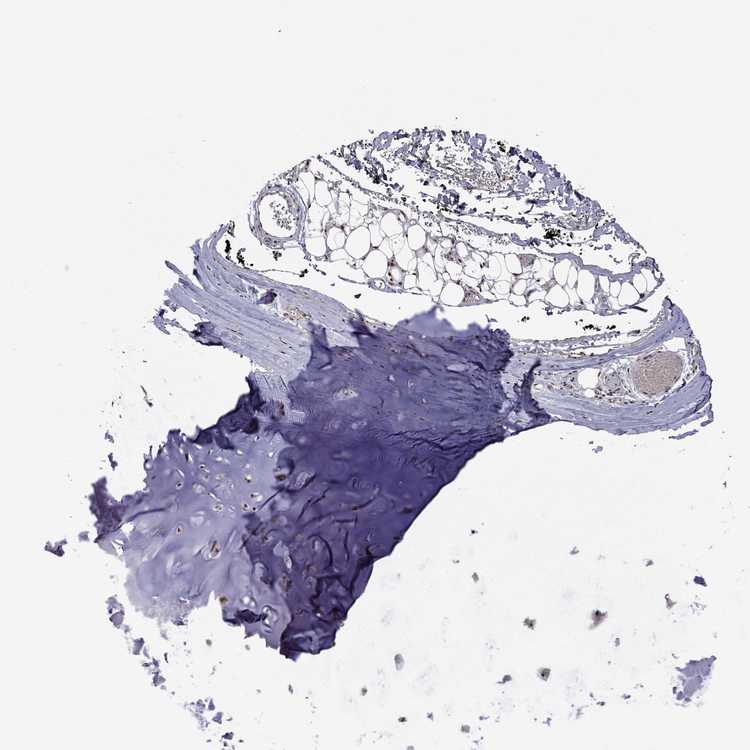

ADIPOSE TISSUE - Antibody stainingi

Antibody staining in the annotated cell types in the current human tissue is reported as not detected, low, medium, or high, based on conventional immunohistochemistry profiling in selected tissues. This score is based on the combination of the staining intensity and fraction of stained cells.

Each image is clickable and will lead to virtual microscopy that enables deeper exploration of all samples and also displays staining intensity scores, fraction scores and subcellular localization as well as patient and tissue information for each sample.

Antibody HPA045192Antibody HPA062363

Adipocytes LowNot detected